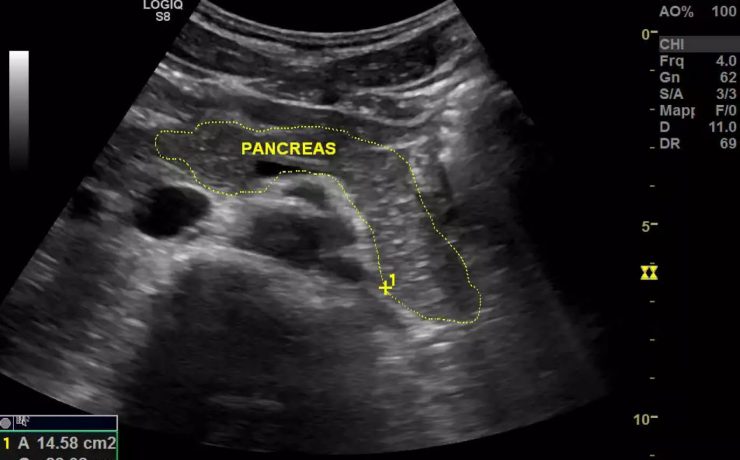

El parénquima esplénico tiene una ecogenicidad similar al hígado y menor que el riñón adyacente. Su valoración ecográfica es útil para confirmar la esplenomegalia y en el estudio de las lesiones esplénicas focales y de los traumatismos abdominales. El aumento del tamaño del bazo, que puede ser difícil de valorar